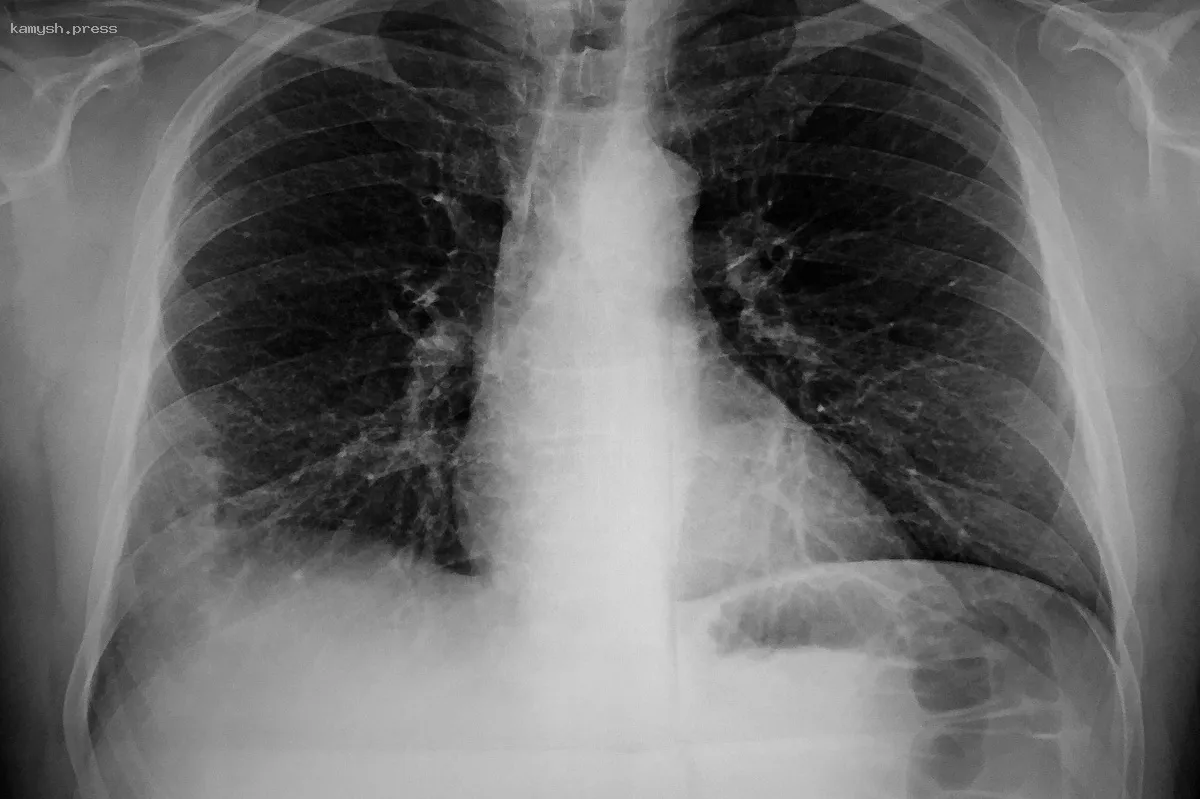

Микоплазменная инфекция может быть возбудителем до 20% случаев пневмоний. Чтобы не упустить развитие болезни, врач Татьяна Ким назвала характерные для состояния симптомы.